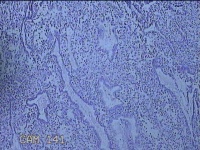

宫腔内容物

性别

女

年龄

47岁

临床诊断

1.异常子宫出血 2.慢性宫颈炎

一般病史

不规则阴道流血21天。

标本名称

大体所见

灰白暗红色不规则碎组织2.5x1.8x0.3cm一堆。

图2